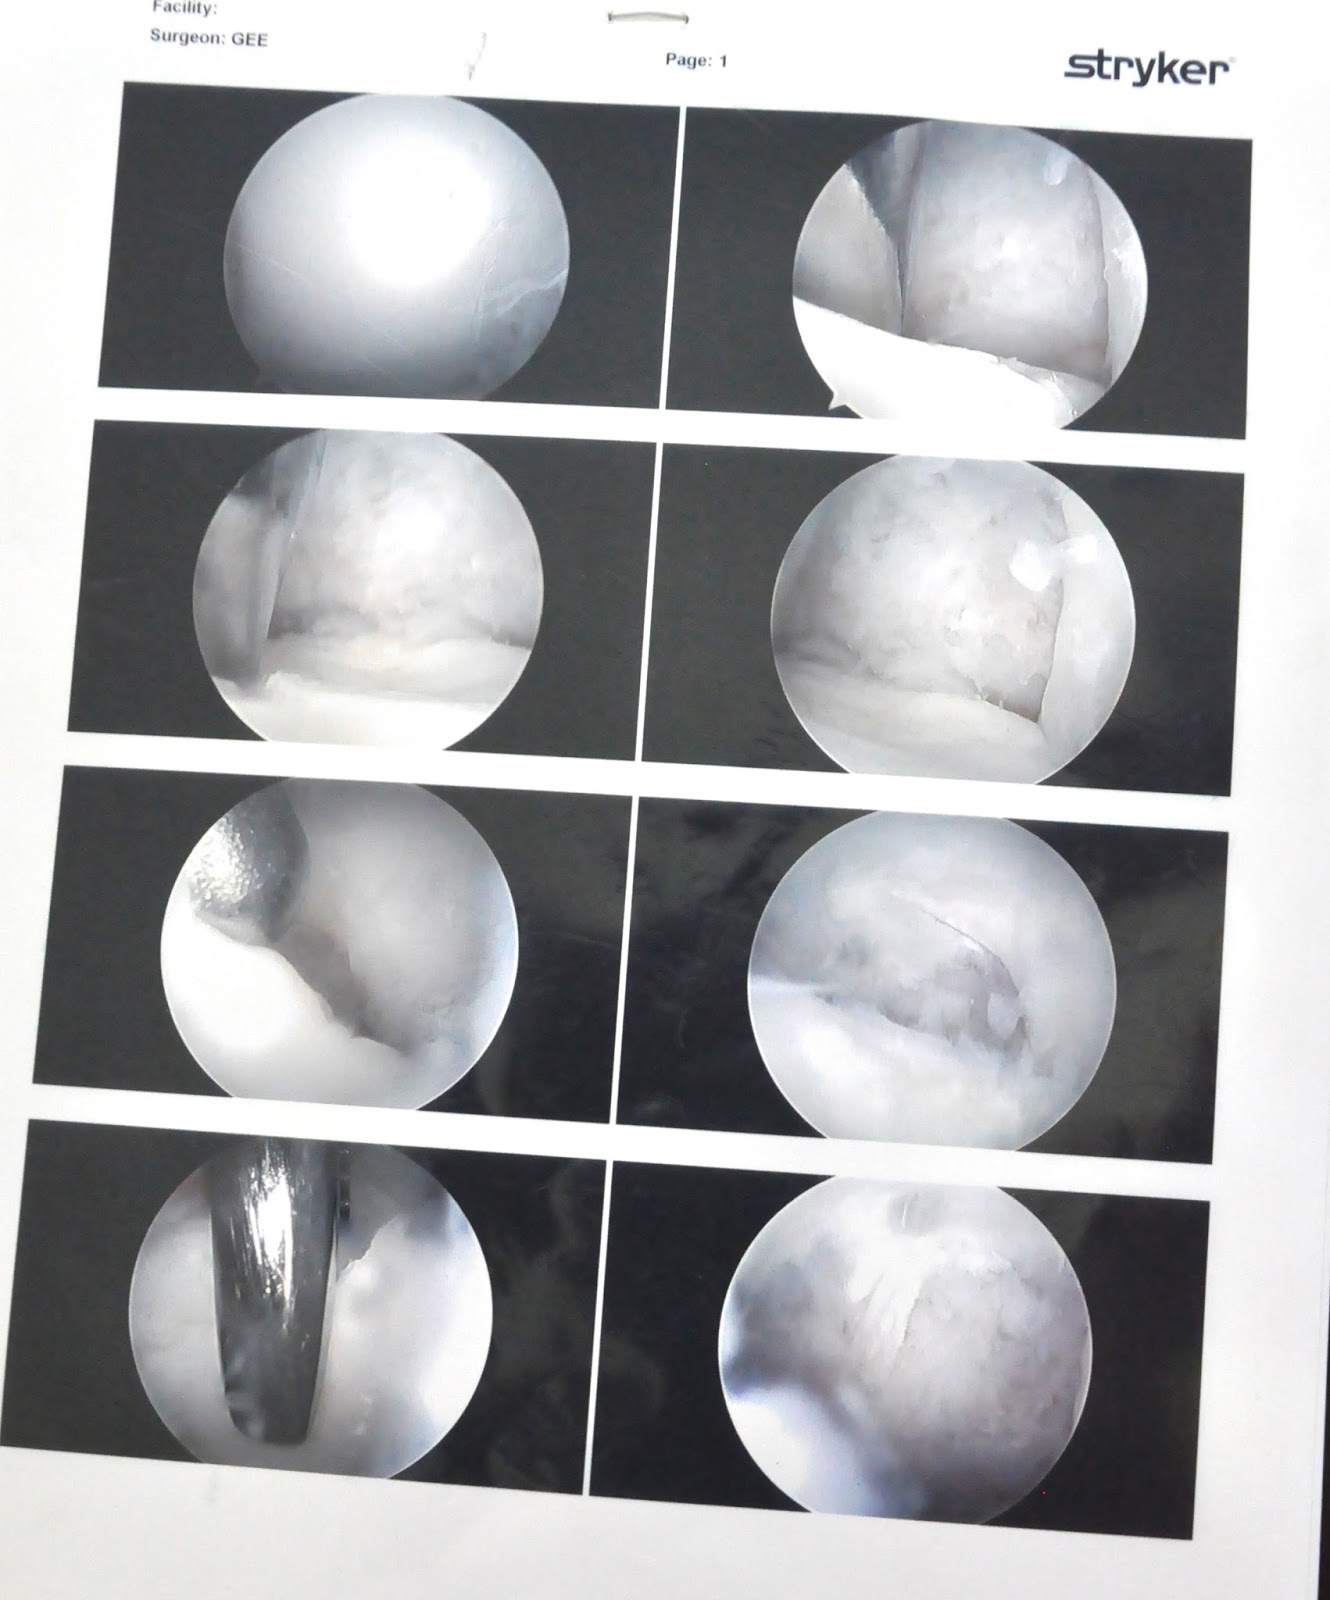

Dr. Gee would later give us photos of the surgery. This first page shows the removal of the cartilage:

On this page, the bone is seen. The sixth photo shows the tool the surgeon used to drill holes into Alyssa's bone. Evidently it was a tool usually used for wrists, but because of her tiny stature, was used for an elbow in this case. The bottom two photos show the holes in the bone after they were drilled.

And finally, the pictures of blood and bone marrow flowing from the holes. According to Dr. Gee, these images were exciting enough to elicit high-fives in the operating room. After all, that blood and marrow were necessary to form a clot and serve as a patch in the place where the damaged cartilage had been.